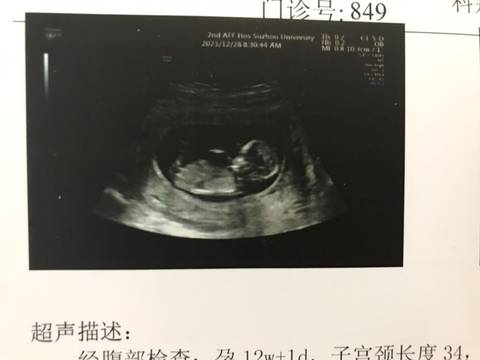

NT检查完能看出男孩女孩吗????

你好。我们是判断不了男宝宝跟女宝宝的,孕期定期检查,我觉得宝宝健康就好的。祝心想事成 。

你好,我们都是一样觉得好奇,确实没什么依据,就个惊喜给自己吧,一切顺利!